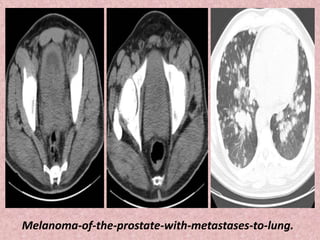

Melanoma-of-the-prostate-with-metastases-to-lung.